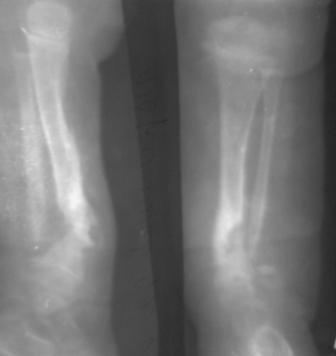

Врожденный ложный сустав голени

Ребенок август 2007г.р. В марте 2008г оперирован детским ортопедом, приглашенным из центра, клиновидная остеотомия, коррекция деформации, фиксация и/м спицами.

Через год рецидив деформации и л/с.

Родители родственники, родился 5 кг, по счету третий, ребенок упитанный (как говорят педиатры - лимфатик), левая нога укорочена на 2,5см. функция коленного и г/с суставов сохранена.